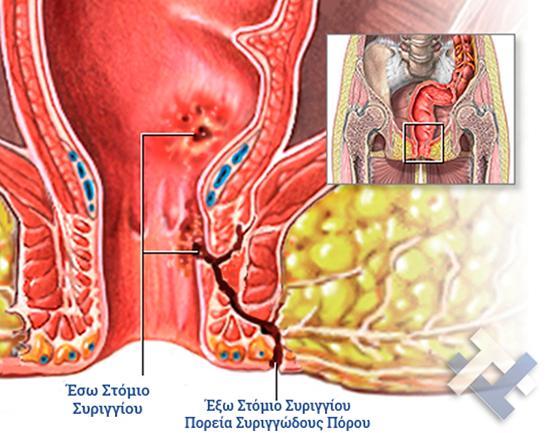

Ο Γενικός Χειρουργός Λιάγκος Γεώργιος MD PhD εκτελεί τις επεμβάσεις Λαπαροσκοπικά, Ενδοσκοπικά, Ανοιχτά Ελάχιστα Επεμβατικά και με Laser. Η θεραπεία εξατομικεύεται σε κάθε ασθενή ανάλογα με τις ανάγκες του. Αναλαμβάνει περιπτώσεις όπως κήλες και κοιλιοκήλες (αντιμετώπιση βουβωνοκήλης, αντιμετώπιση ομφαλοκήλης, θεραπεία επιγαστρικής κήλης, κήλη των αθλητών (Σύνδρομο κοιλιακών προσαγωγών), αντιμετώπιση μετεγχειρητικής κήλης, θεραπεία Μηροκήλης), πέτρες στη χοληδόχο κύστη, λαπαροσκοπική χολοκυστεκτομή, αντιμετώπιση Κύστη Κόκκυγος με λέιζερ (laser), παθήσεις πρωκτού, χειρουργική laser σύγχρονων κυκλικών ινών (αιμορροΐδες αντιμετώπιση, θεραπεία αιμορροϊδων με laser (LHP), αφαίρεση αιμορροΐδων με υπερήχους (HALL-RAR), χωρίς Χειρουργείο με ελαστικούς δακτυλίους (Τεχνική BARON-RBL), θεραπεία ραγάδας πρωκτού (Ραγάδα δακτυλίου), θεραπεία περιεδρικού συριγγίου, θεραπεία περιεδρικού αποστήματος, κονδυλώματα πρωκτού Θεραπεία, δερματικό ράκος (Skin tag) εκτομή, αντιμετώπιση Kνησμού, καρκίνος πρωκτού θεραπεία), παθήσεις Δέρματος, χειρουργική με laser CO2, αφαίρεση μορφωμάτων δέρματος - βιοψίες, αφαίρεση ελιάς (Σπίλου), σμηγματογόνος κύστης θεραπεία, αφαίρεση λιπώματος, είσφρυση όνυχος χειρουργείο, καρκίνος δέρματος θεραπεία, οξεία σκωληκοειδίτιδα, παθήσεις Λεπτού και Παχέος Εντέρου, ειλεός λεπτού εντέρου, εκκολπωμάτωση (Εκκολπωματίτιδα) σιγμοειδούς, καρκίνος παχέος εντέου, κολοστομίες, port χημειοθεραπείας κ.α.

Ο Γενικός Χειρουργός Λιάγκος Γεώργιος MD PhD εκτελεί τις επεμβάσεις Λαπαροσκοπικά, Ενδοσκοπικά, Ανοιχτά Ελάχιστα Επεμβατικά και με Laser. Η θεραπεία εξατομικεύεται σε κάθε ασθενή ανάλογα με τις ανάγκες του. Αναλαμβάνει περιπτώσεις όπως κήλες και κοιλιοκήλες (αντιμετώπιση βουβωνοκήλης, αντιμετώπιση ομφαλοκήλης, θεραπεία επιγαστρικής κήλης, κήλη των αθλητών (Σύνδρομο κοιλιακών προσαγωγών), αντιμετώπιση μετεγχειρητικής κήλης, θεραπεία Μηροκήλης), πέτρες στη χοληδόχο κύστη, λαπαροσκοπική χολοκυστεκτομή, αντιμετώπιση Κύστη Κόκκυγος με λέιζερ (laser), παθήσεις πρωκτού, χειρουργική laser σύγχρονων κυκλικών ινών (αιμορροΐδες αντιμετώπιση, θεραπεία αιμορροϊδων με laser (LHP), αφαίρεση αιμορροΐδων με υπερήχους (HALL-RAR), χωρίς Χειρουργείο με ελαστικούς δακτυλίους (Τεχνική BARON-RBL), θεραπεία ραγάδας πρωκτού (Ραγάδα δακτυλίου), θεραπεία περιεδρικού συριγγίου, θεραπεία περιεδρικού αποστήματος, κονδυλώματα πρωκτού Θεραπεία, δερματικό ράκος (Skin tag) εκτομή, αντιμετώπιση Kνησμού, καρκίνος πρωκτού θεραπεία), παθήσεις Δέρματος, χειρουργική με laser CO2, αφαίρεση μορφωμάτων δέρματος - βιοψίες, αφαίρεση ελιάς (Σπίλου), σμηγματογόνος κύστης θεραπεία, αφαίρεση λιπώματος, είσφρυση όνυχος χειρουργείο, καρκίνος δέρματος θεραπεία, οξεία σκωληκοειδίτιδα, παθήσεις Λεπτού και Παχέος Εντέρου, ειλεός λεπτού εντέρου, εκκολπωμάτωση (Εκκολπωματίτιδα) σιγμοειδούς, καρκίνος παχέος εντέου, κολοστομίες, port χημειοθεραπείας κ.α.